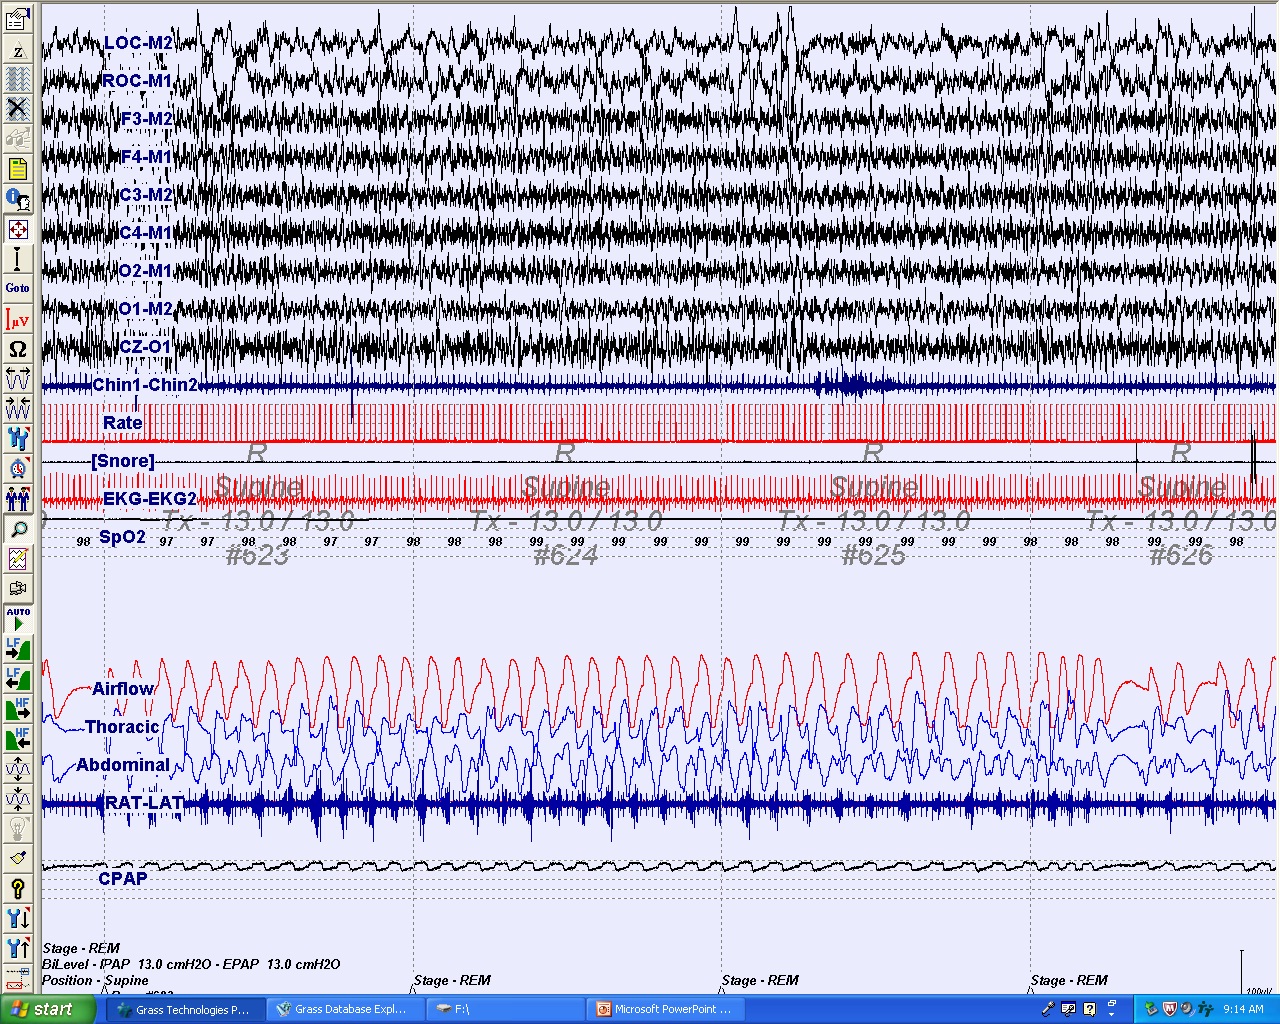

The patient was subsequently referred for a CPAP titration sleep study. Panel C demonstrates a 2-minute epoch of a nocturnal PSG for CPAP titration that identified an optimal treatment pressure of 13 cm H2O. This epoch demonstrates that CPAP treatment at 13 cm H2O was therapeutic while the patient is in rapid eye movement sleep and supine.